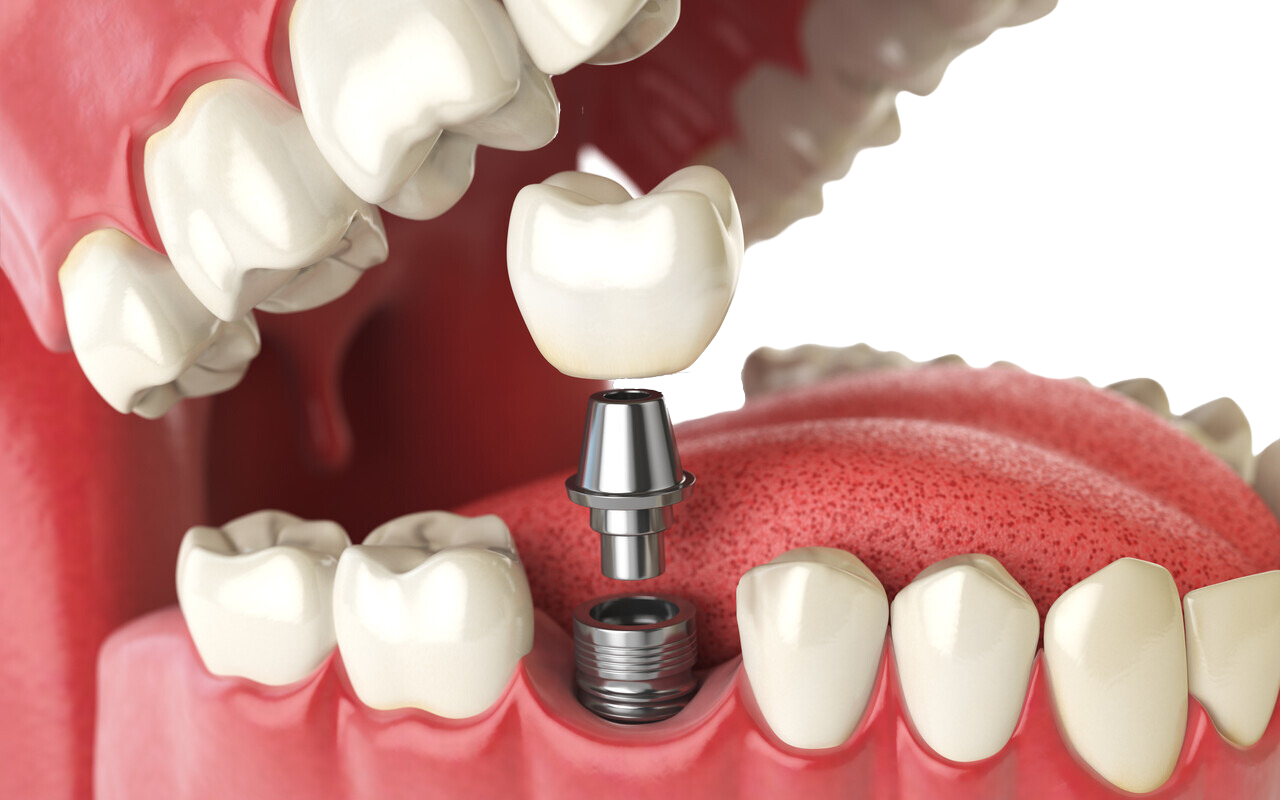

With over a decade of experience in all fields of dentistry, Dr. White has a particular passion for cosmetic procedures, including dental implants, Lumineers, and Invisalign. His extensive experience in private practice and dedication to helping those in need have honed his skills in delivering exceptional dental care. Patients choose Dr. White for his ability to not only alleviate pain quickly but also to dramatically improve their smiles and quality of life through expertly performed dental implants.